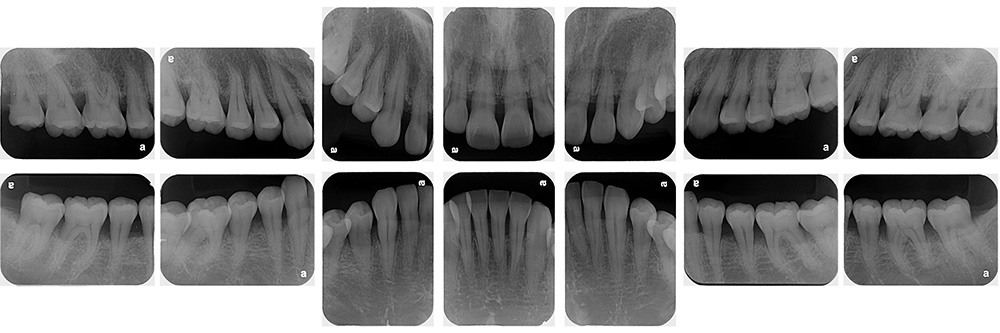

術前

世代・性別

60代男性

主訴

歯ブラシで出血するので見てほしい

治療内容

ブラッシング指導、歯周基本治療、虫歯治療、根管治療、補綴治療

治療期間

6ヶ月

治療費

保険適応内

治療のリスク

治療後にしみる・痛みが出ることがある